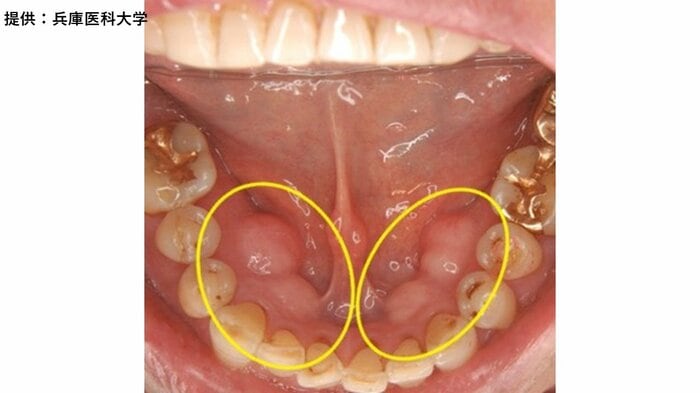

・下の歯の内側の歯肉部(左右)…「下顎(かがく)隆起」と呼ばれる

・その他、下の歯の外側の歯肉部や、上の歯の内・外側の歯肉部にできる人もいる。左右対称に生じることが多い(特定の名称はなく、単に「骨隆起」と呼ばれることも)

・小さな出っ張りが重なって、モコモコと膨らんだように見えることもある

池邉理事長は「食事や発音を妨げるほど大きくなるものはほとんどない」とし、岸本常任理事も「左右の下顎隆起がくっつきそうになるくらい増大するケースもまれにあるが、高さが1センチを超えるほど大きくなることは通常めったにない」と話す。